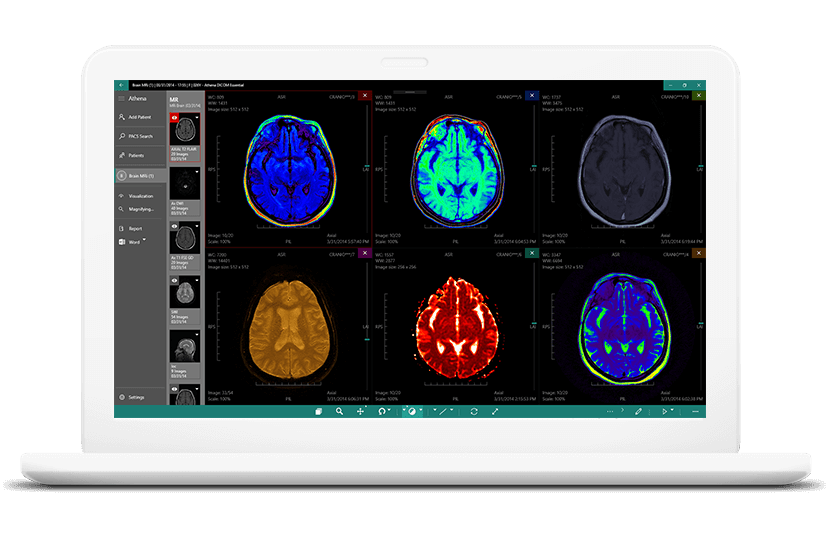

Лазерная камера сетевая для печати изображений на пленке стандарт dicom